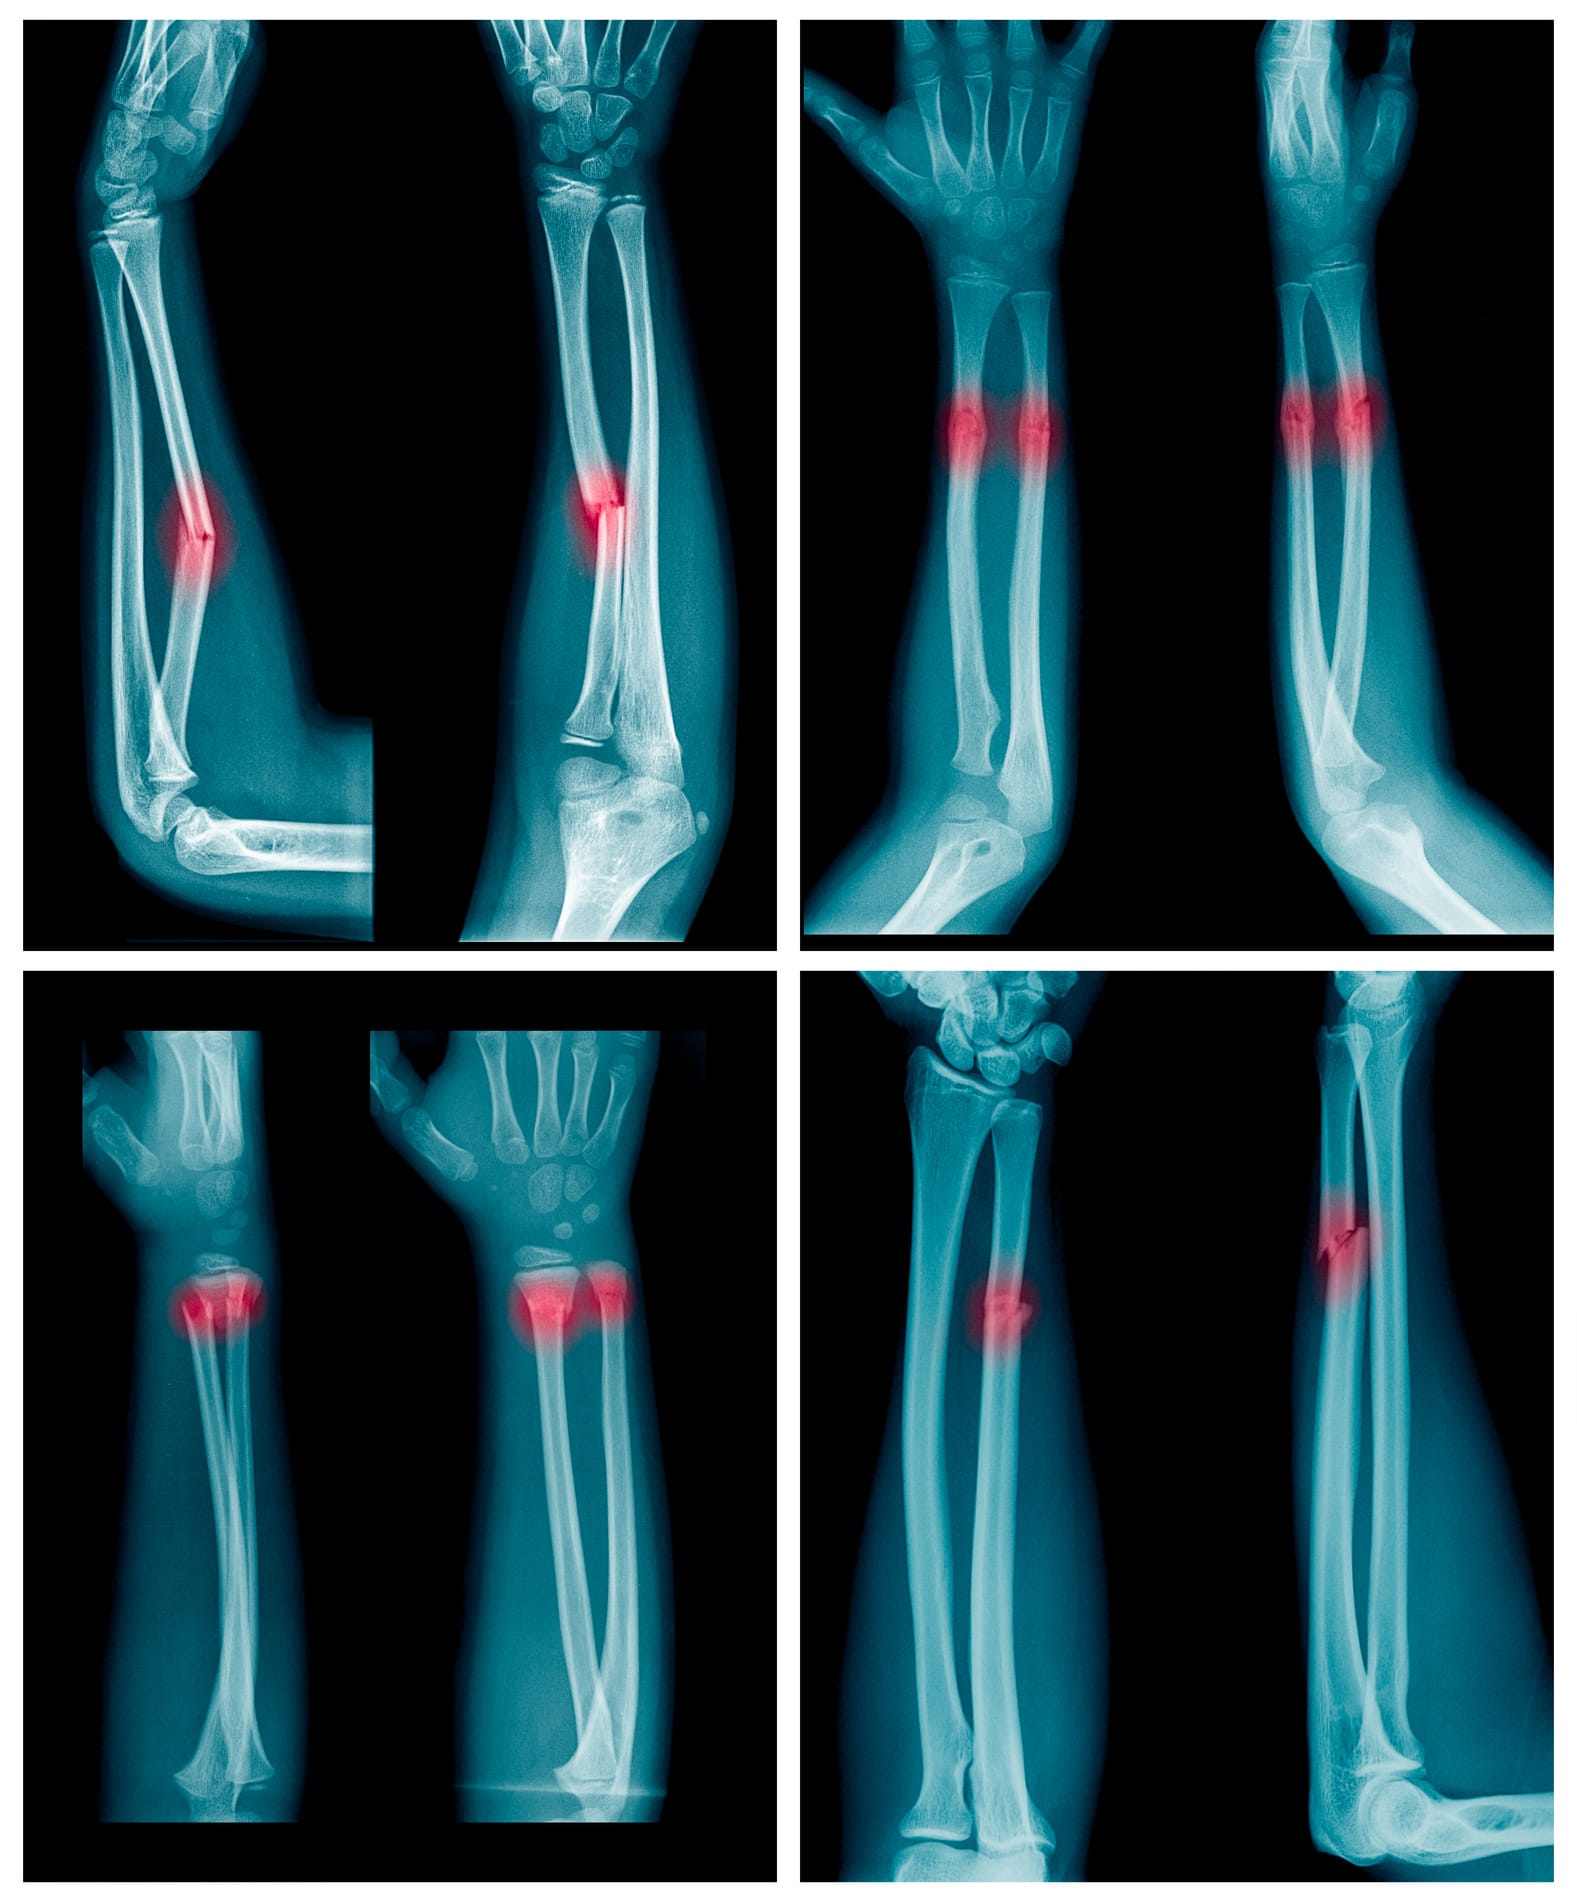

She studies skeletal trauma – that is, the broken bones of the dead. Her research is mostly all in children. Her key enquiry is investigating the difference between the bones of a child killed accidentally in a fall and a child killed by “non-accidental blunt-force trauma”, which translated to plain English means being hit, stomped on, kicked, thrown or otherwise assaulted in the context of child abuse.

Paediatric skeletal trauma is one of five projects (all to do with skeletal trauma, or broken bones, of some kind) Rowbotham is involved in out of the VIFM. There are 15,000 cases of physical child abuse a year in Australia, most not fatal, but “it’s an important social issue”, she says, “and these types of cases are particularly complex for medico-legal practitioners. How can we differentiate skeletal injuries that result from an accidental fall with injuries that result from physical abuse? It’s a challenging question for many reasons.”

She says children’s bones are difficult to study as well; they’re different to adult bones in that they’re still developing. “The bones of a child are more elastic than an adult. So when force is applied to a child’s bones, the bones will bend before they break, unlike an adult’s bones, where they’ll simply break.

“This difference in biology means fractures appear differently in a child’s skeleton. The body proportions of a child are also different. Infants and very young children have heavier heads, so their centre of gravity is different to an adult’s, and this can influence how they land when falling,” Rowbotham says.

“The way our bones fuse and develop with age also influences where we see fractures, and how those fractures heal. It is in some ways much more complicated to look at a child’s skeleton.”

Rowbotham’s method for comparing injuries and mapping the connections between them is relatively simple, but it’s a novel approach. She uses post-mortem computed tomography (PCMT) scans and coronial data to look at cases of skeletal blunt-force trauma to identify patterns of injury.